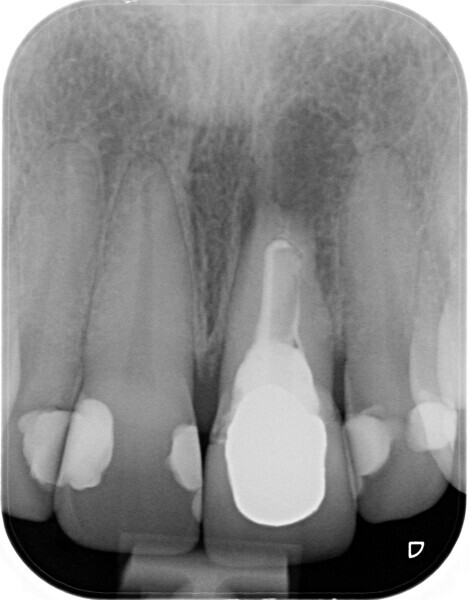

Fig. 2: Initial radiographic examination.